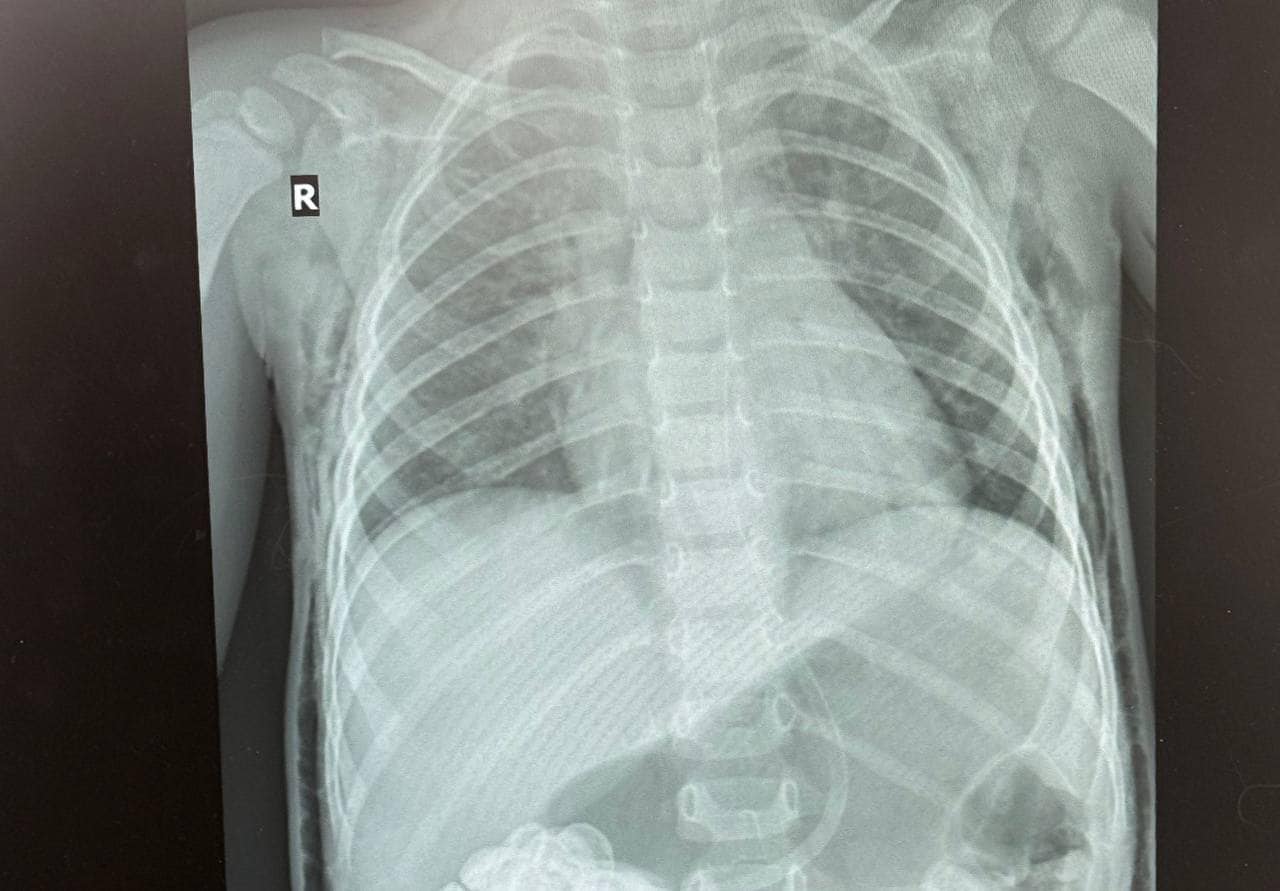

У рідному місті, де Луку під час стоматологічного лікування інтубували, мама хлопчика помітила, що у сина почало боліти горло, з'явилися набряки на шиї, голові та обличчі, а дихання стало утрудненим. Термінове звернення до місцевої лікарні виявило накопичення повітря в середостінні, під шкірою голови, шиї та грудної клітки, що свідчило про порушення цілісності дихальних шляхів.

Луку терміново доставили до «Охматдиту», де спеціалісти виявили розрив трахеї довжиною 2,5-3 см. Того ж дня була проведена операція, під час якої медики успішно зашили і відновили цілісність трахеї.